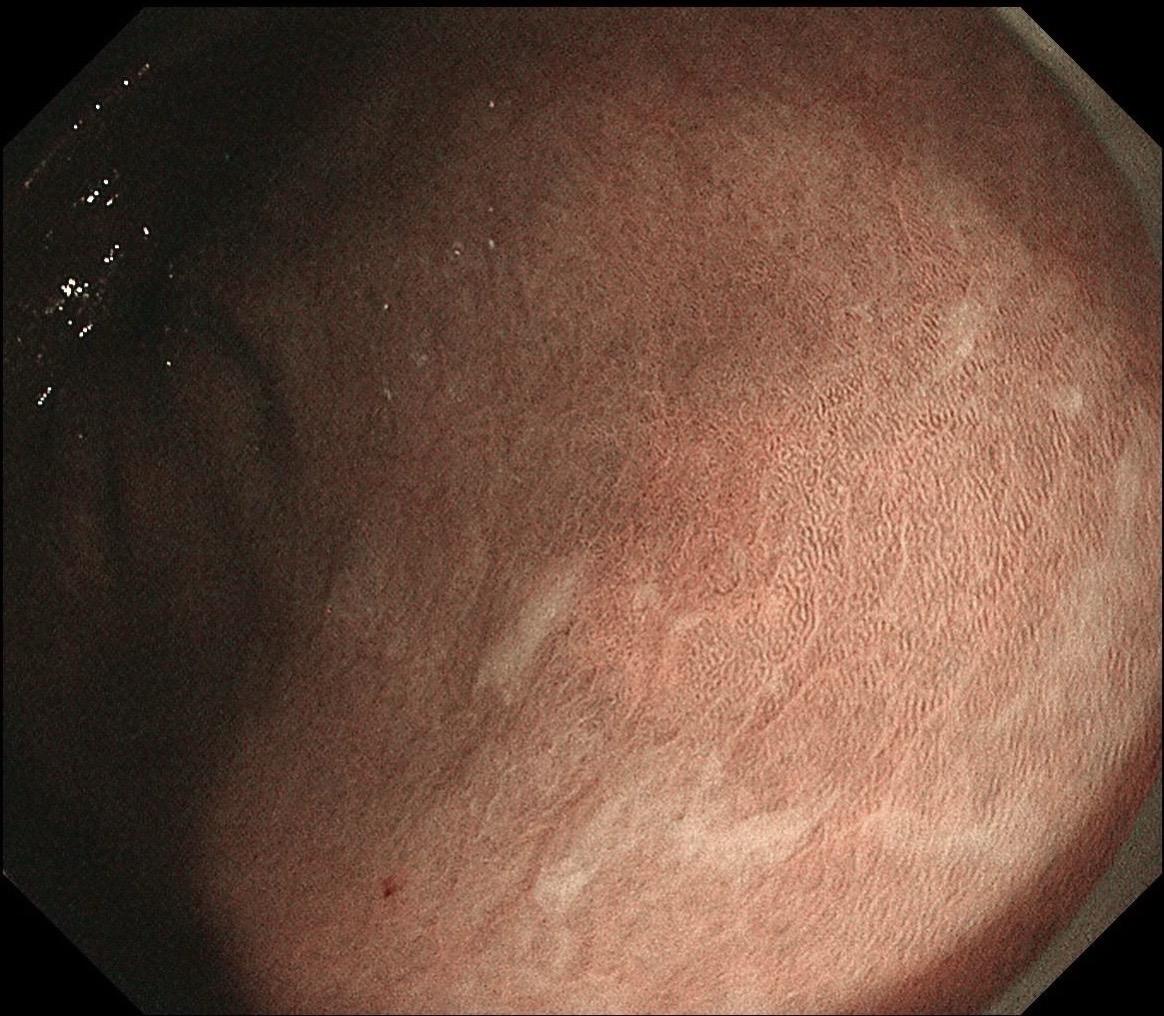

男,40岁,胃双发褪色调病变。慢性胃炎复查,3年前胃镜未见异常,Hp阳性背景,萎缩不明显,胃体下部大弯见一褪色调病变,浅凹陷,5mm左右,换用放大内镜观察,表面结构缺失,血管异型明显,未分化可能性大……胃窦后壁见一白斑,无高度差,NBI浅茶色,放大草草看了下,似有边界,IP增宽,活检待病理……小哥哥胖得几乎没脖子,腹式呼吸太明显~😖